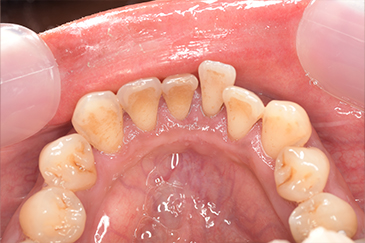

CASE 3

| 年齢・性別 | 30代・女性 |

|---|---|

| 主訴 | 定期検診 |

| 治療内容 | PMTC |

| 治療期間 | 60分 |

| 治療費 | 5,750円 |

| リスク・副作用 | しみる可能性があります。 |

| 治療方針 | PMTCでステインの除去。 |

| 担当者所見 | ステインが付きやすいため、3カ月毎の定期検診で除去する。 |